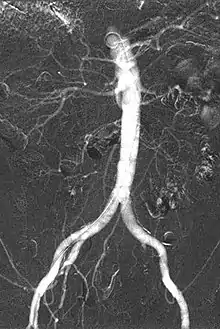

Carbon dioxide angiography is a diagnostic radiographic technique in which a carbon dioxide (CO2) based contrast medium is used - unlike traditional angiography where the contrast medium normally used is iodine based – to see and study the body vessels.[1] Since CO2 is a non-radio-opaque contrast medium, angiographic procedures need to be performed in digital subtraction angiography (DSA).

Carbon dioxide is a negative contrast medium and it has a low radiopacity (while iodinated contrast media are defined as positive contrast media due to their high radiopacity). Contrast is caused by the different X-ray absorption coefficients between the tissue and the contrast agent. In the vascular imaging results produced using CO2, vessels look brighter rather than the surrounding tissues, because the contrast medium absorbs less X-ray radiations rather an iodine-based contrast medium, where the vessel are displayed in black.

The CO2 does not mix with blood. At atmospheric pressure CO2 is in gaseous form and, when it comes out from the catheter, it forms a train of bubbles which displaces blood, causing a transient ischemia, in relation to the bloodstream (systolic pressure). When added together by DSA “stacking” software,[5] the result is a composite diagnostic image of the frames.

CO2 is 400 times less viscous than iodinated contrast medium, allowing its injection through devices with a very little inner lumen, as microcatheters, or, even, with other devices inserted in the catheter, as guidewires, balloons or as in atherectomy procedures. The low viscosity of CO2 makes it easy to pass through small vessels, visualizing tight stenosis, collaterals, small bleedings and endoleaks in AAA procedures.